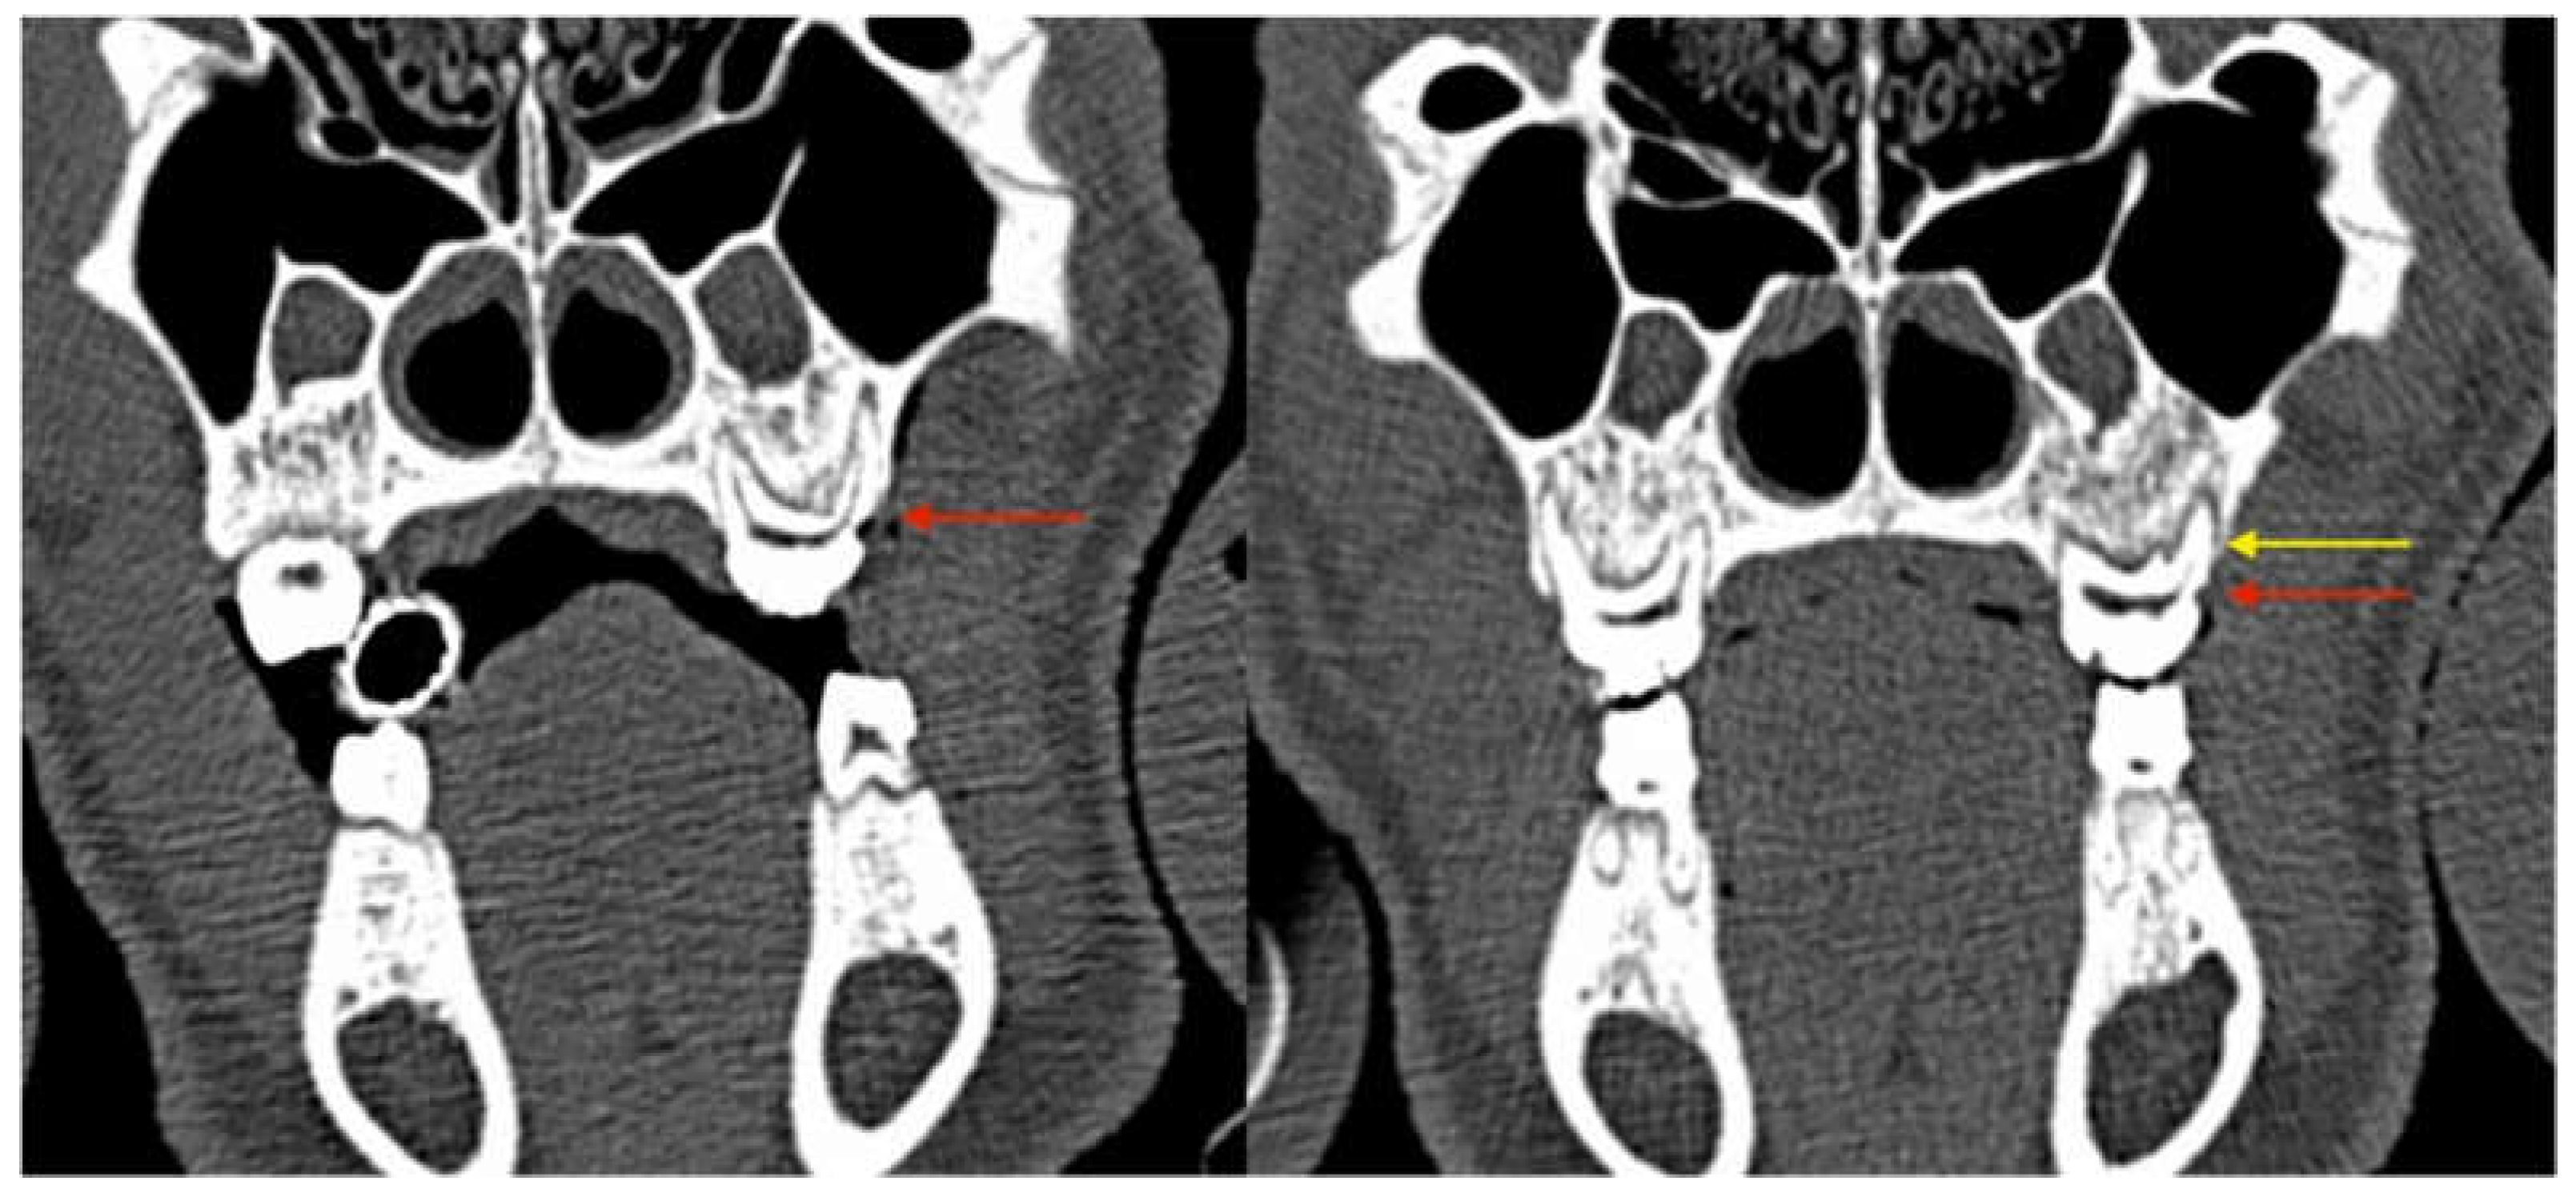

3.2.3. Radiological Evaluation